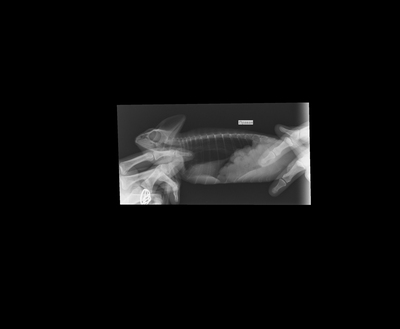

Было назначено: сдача стула на паразитов, рентген плюс анализ крови, чтобы хоть как-то попытаться определить причину болезни.

Проблем с паразитами не было, а вот на рентгене был какой то не переваренный кусок еды. Это могло быть что-то из декора, что он по глупости съел и теперь не может из себя вывести. Тогда пришлось бы делать операцию.